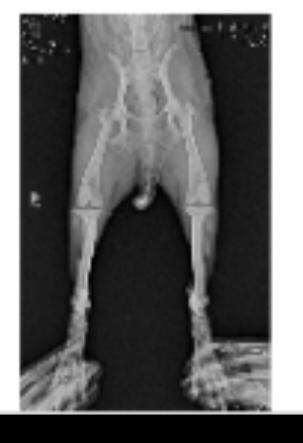

강아지 엑스레이 슬개골 탈구랑 십자인대 봐주세요ㅠㅠ

저희집 강아지가 공놀이를 좋아하고 산책할때 좀 흥분해서 뛰는 편입니다ㅠㅠ 그래서 어릴때부터 슬개골이 좋지는 않고 1기에서 2기로 진행되고 있다는 얘기는 왕왕 들었는데 항상 꼬리를 들고 있는 앤데 꼬리도 내려가고 오른쪽 다리를 아파하는거 같고 산책나가서도 앉고 안걸을려고 해서 병원을 갔는데 슬개골 탈구랑 십자인대도 좀 안좋은거 같다고 영상기기 있는 곳애 가보라고 하셔서 가서 엑스레이를 찍어봤습니다..

근데 그 병원에서는 슬개골이 안좋긴한데 삔거 같다고만 하셔서 약을 받아왔는데 그 뒤로 강아지가 꼬리를 드니깐 화들짝 놀라면서 싫어하는거 같더라구요...

그래서 또 다른 병원을 갔느데 거기에는 또 영상기기가 없는데 슬개골탈구다 수술해야한다고만 얘기하셔서 혼란스럽네요ㅠㅠㅠ

엑스레이 한번만 봐주실 수 있나요ㅠㅠ

슬개골 탈구는 원래 엑스레이로 진단하는 질환이 아니라 주치의의 촉진으로 진단하는 질환입니다. 엑스레이는 이차적 혹은 별도로 십자인대의 이상이나 골절, 주변 연부조직, 관절면 등 유사한 증상을 보일 수 있는 동반 질환을 감별하기 위한 검사이기에 슬개골 탈구 자체의 진단에는 필수적인 검사는 아닙니다.